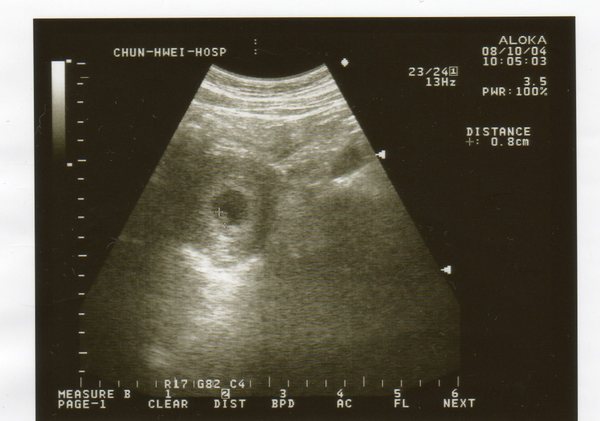

今天去春暉回診

中間黑黑的一圈醫生說是羊水

左下角一個小點是寶寶

現在只有0.8公分大

醫生說照這個大小來看 應該只有六週大小